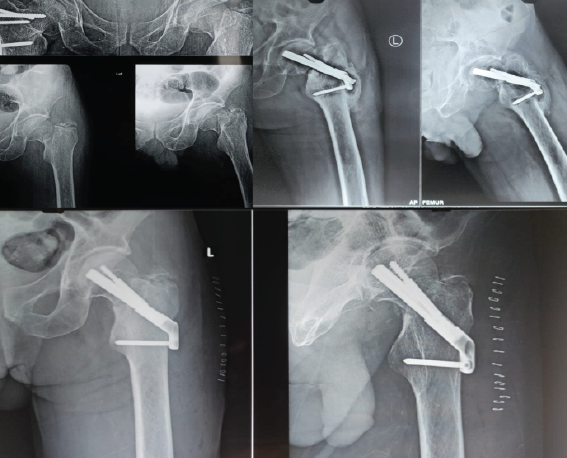

Case 7

A 60-year-old female with osteoporosis sustained a displaced Garden’s type IV, Pauwel’s type III fracture. The fracture was fixed in neutral position with the FNS device, but the bolt and anti-rotation screw were placed too anteriorly, leaving a superolateral void at the head–neck junction. Although union was achieved at 5 months, the fracture underwent varus collapse and significant neck shortening, with radiographs showing a widening gap between the plate and lateral femoral cortex compared to immediate post-operative images (Fig. 6). This case emphasizes the importance of central implant positioning and valgus fixation in osteoporotic bone and perhaps a lower threshold for choosing replacement over fixation in osteoporotic bone.

Figure 6 Top left: Pre-operative radiographs of Case 7; top center: immediate post-operative AP radiograph of the fracture; top right: union with a shortened neck and varus collapse. Bottom left: Pre-operative radiograph of Case 8; bottom center: Intraoperative C-arm images following reduction to neutral- clearly showing a supero-lateral bony void; bottom right: varus collapse and neck shortening noticed at 7 months.

Case 8

A 66-year-old female sustained a valgus-impacted Garden’s type I, Pauwel’s type I fracture. During fixation, an attempt was made to correct the valgus to a neutral position, which created a superolateral void and reduced anti-rotation screw purchase. This destabilized the lateral hinge and predisposed the fracture to collapse. By 7 months, the fracture underwent varus collapse and shortening, evident from reduced space between the lateral end of the bolt and barrel compared to immediate post-operative images (Fig. 6). In hindsight, in situ fixation or valgus fixation would likely have been preferable in such cases.